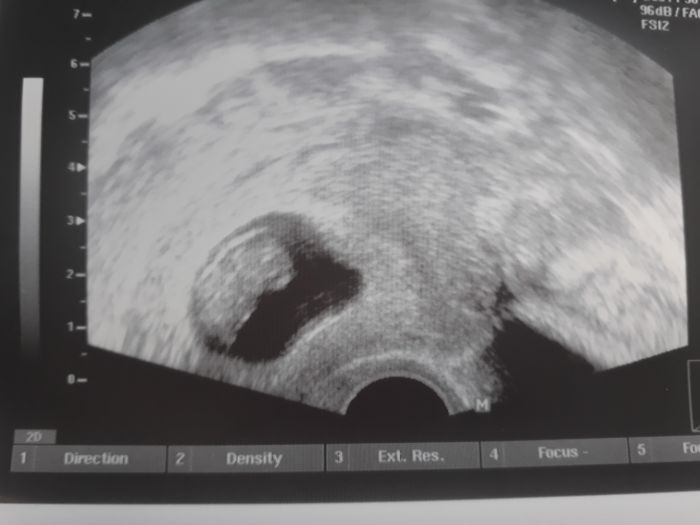

Tak jsem byla predevcirem na kontrole. Jsem 9+2. V podbrisku me taky poboliva, ale pry je to tou roztahující se dělohou. Na nevolnosti mi dost pomáhá mátový čaj. A jinak měříma 2,5 cm a vypadáme takto

krasna fotecja[1118104]